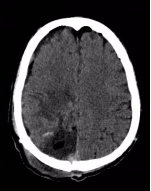

△术后头颅CT显示畸形团切除彻底

手术团队奋战8小时,终于在少量出血的情况下完整切除脑动脉畸形,并清除颅内血肿。

术后患者情况明显改善,神志清晰,左侧肢体肌力恢复至约3-4级,即将出院。